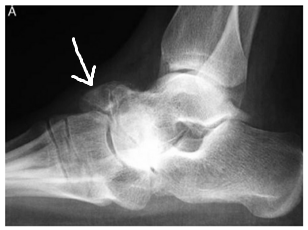

(圖解)圖為穆勒─魏斯氏症患者之X光,箭頭指的位置可以看到在腳背已經有贅骨的生成了